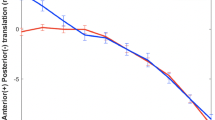

Moreover, the MFRs of the static single-leg-stand and the stance phase of level-walking in vivo are highly predictable by the external frontal-plane lever arm (EFL) calculated from frontal-plane skeleton dimensions. Linear regression analysis revealed highly significant positive correlations of the knee-width-normalized EFL/w with the knee-width-normalized knee-internal frontal plane lever arms IFLSLS/w and IFLLW/w calculated from in-vivo-measurement data, for the static single-leg-stand (intercept = 0.341; 68.3%CI, 0.304–0.379; 95%CI, 0.259–0.423; EFL/w = 1.85·IFLSLS/w + 0.341; t7 = 9.9; P < 0.001; R2 = 0.90) and for the stance phase of level-walking (intercept = 0.349; 68.3%CI, 0.308–0.391; 95%CI, 0.259–0.440; EFL/w = 2.12·IFLLW/w + 0.349; t7 = 9.1; P < 0.001; R2 = 0.88). IFLSLS/w and IFLLW/w are proportional to the respective medial compartment force ratio (MFR, Eq. (4)). The one EFL/w corresponding to MFR = 50% results from the intercepts of the latter two relationships to EFL/w = 0.341 for the static single-leg-stand, and, very similar, EFL/w = 0.349 for the stance phase of level-walking (Fig. 4 mid/right). Balanced loads during the stance phase of level-walking thus may be expected if the EFL is 0.349 times the femur epicondyle distance w, which is the sought-after EFL for osteotomy around the knee.

Relationships of the skeleton-derived EFL to KAM and MFR. Left: Relationships between the external Knee Adduction Moment at static single-leg-stand (KAMS), calculated from frontal-plane skeleton dimensions, and both published KAM peaks measured during gait analysis. Mid and right: Relationships between the Medial compartment Force Ratio (MFR) calculated from published in-vivo-measurement data, and the knee-width-normalized External Frontal plane Lever arm (EFL) calculated from frontal-plane skeleton dimensions (MFR-scale assuming c = 1.5). The respective relationships for the static single-leg-stand (mid) and for the stance phase of level-walking, including both single-support- and double-support-phases (right), are very similar. All data originate from the same nine subjects, the number within each mark corresponds to the number of the subject denotation

Furthermore, the skeleton-derived static knee adduction moment KAMS, equal to EFL in the unit [%Ht], turned out highly predictive for the published knee adduction moment (KAM) measured during gait analysis. Highly significant linear correlations of KAM with KAMS were found for the maximum KAM (estimate: 68.3%CI; KAM = 1.26·KAMS-0.61%BWHt ± 0.44%BWHt; t7 = 7.1; P < 0.001; R2 = 0.88), and especially for the first KAM peak, values being even almost equal (Fig. 4 left) (estimate: 68.3%CI; KAM = 1.13·KAMS-0.33%BWHt ± 0.40%BWHt; t7 = 7.0; P < 0.001; R2 = 0.88).